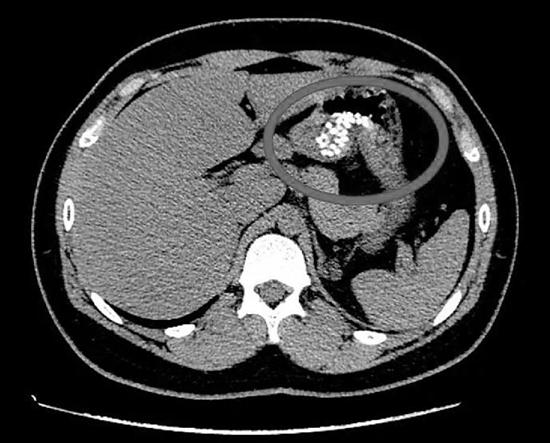

中高考要到了,如何科学调整心理情绪,成为家长和孩子共同面临的考题。最近,浙江大学医学院附属邵逸夫医院急诊室来了一个16岁的杭州初中生,说腹部疼痛,一直呕吐……。从CT片可以看到一堆白色的小点点,这提示胃内大量颗粒状致密影。(见图)

消化科值班医生看着CT片,冒出了很多个想法:珍珠奶茶?豆子?纽扣?巴克球(一种带有磁性的金属实心圆球)?他再和男孩对话,仔细追问病史,要求患者将这两天吃进去的食物都回顾一遍,然而,没有任何有价值的信息。

邵逸夫医院急诊室何医生也与男孩的妈妈取得了联系,对于和孩子吵架是否因学业或其他问题,她不愿意谈论,只是表示很后悔。随后,医生再次给男孩复查CT,发现药片大部分已进入了小肠、大肠,于是给予导泄、大量补液,第二天,男孩的症状明显缓解,复查指标也较之前明显转好。